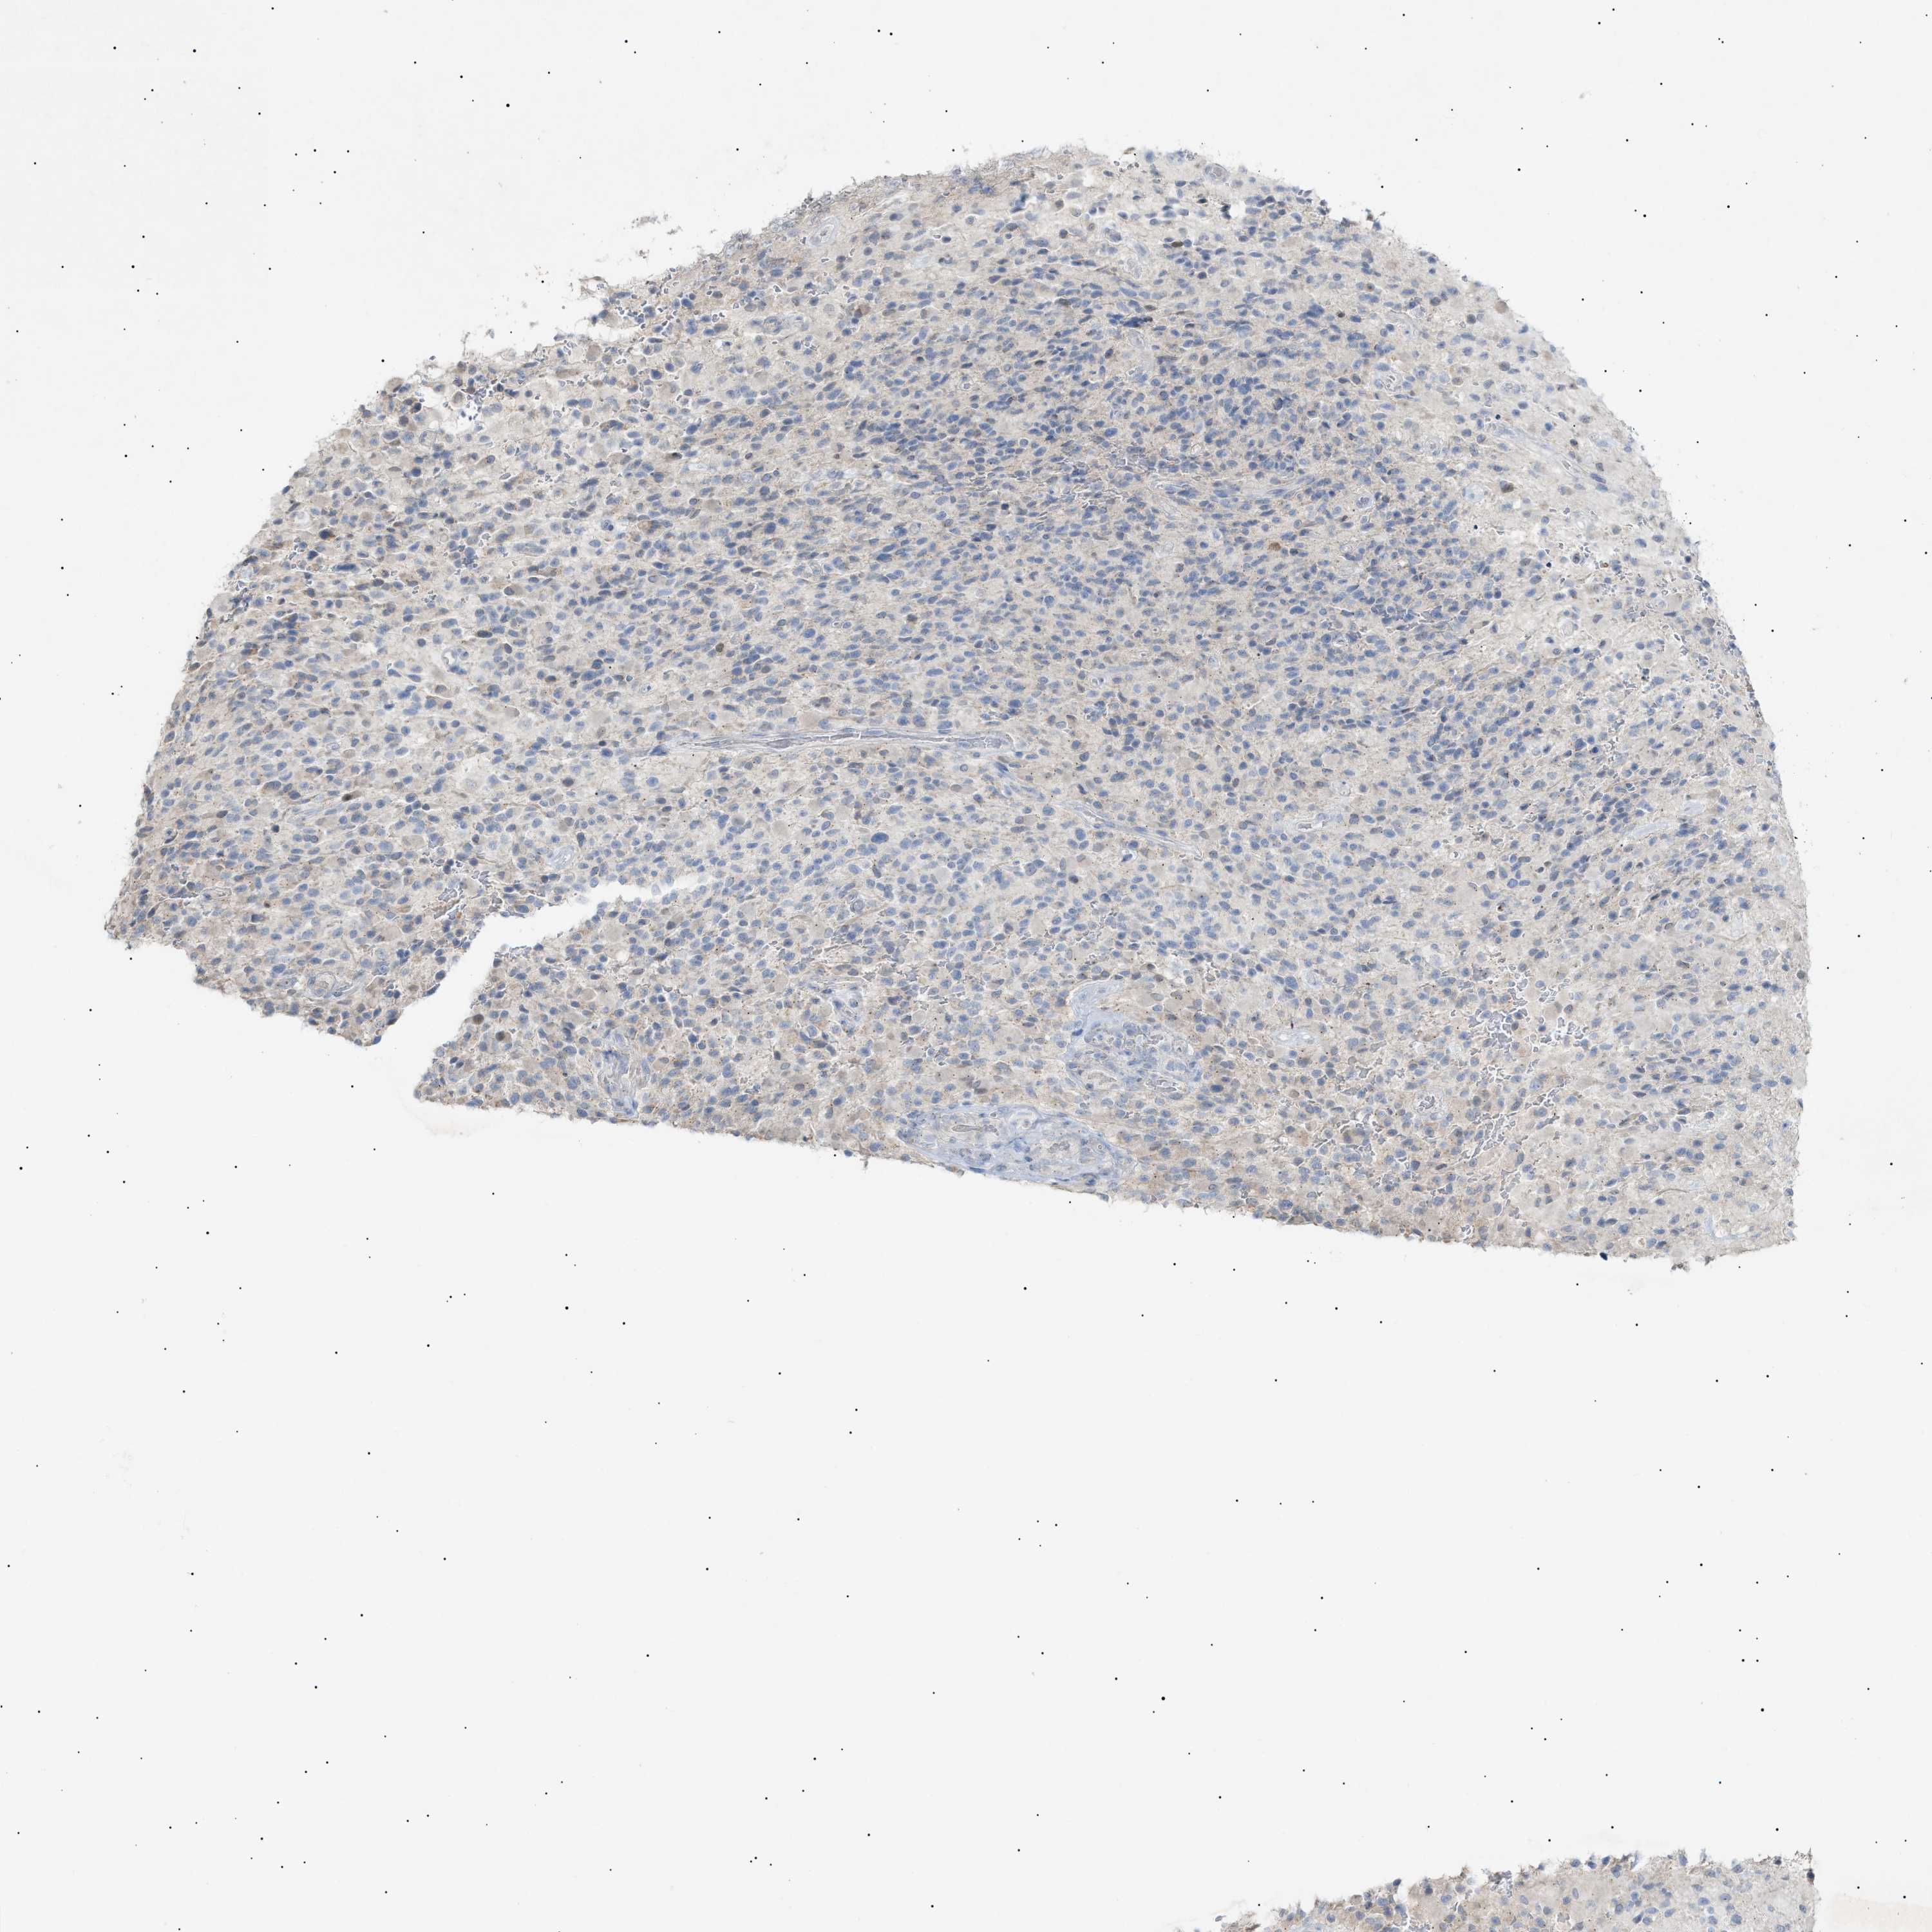

GLIOMA - Protein expressioni

A mouse-over function shows sample information and annotation data. Click on an image to view it in a full screen mode. Samples can be filtered based on level of antibody staining by selecting one or several of the following categories: high, medium, low and not detected. The assay and annotation is described here.

Note that samples used for immunohistochemistry by the Human Protein Atlas do not correspond to samples in the TCGA dataset.

Antibody stainingi

Antibody staining in the annotated cell types in the current human tissue is reported as not detected, low, medium, or high, based on conventional immunohistochemistry profiling in selected tissues. This score is based on the combination of the staining intensity and fraction of stained cells.

Each image is clickable and will lead to virtual microscopy that enables deeper exploration of all samples and also displays staining intensity scores, fraction scores and subcellular localization as well as patient and tissue information for each sample.

Antibody HPA015064

Antibody HPA071684

Glioma, malignant, High grade

Glioma, malignant, Low grade